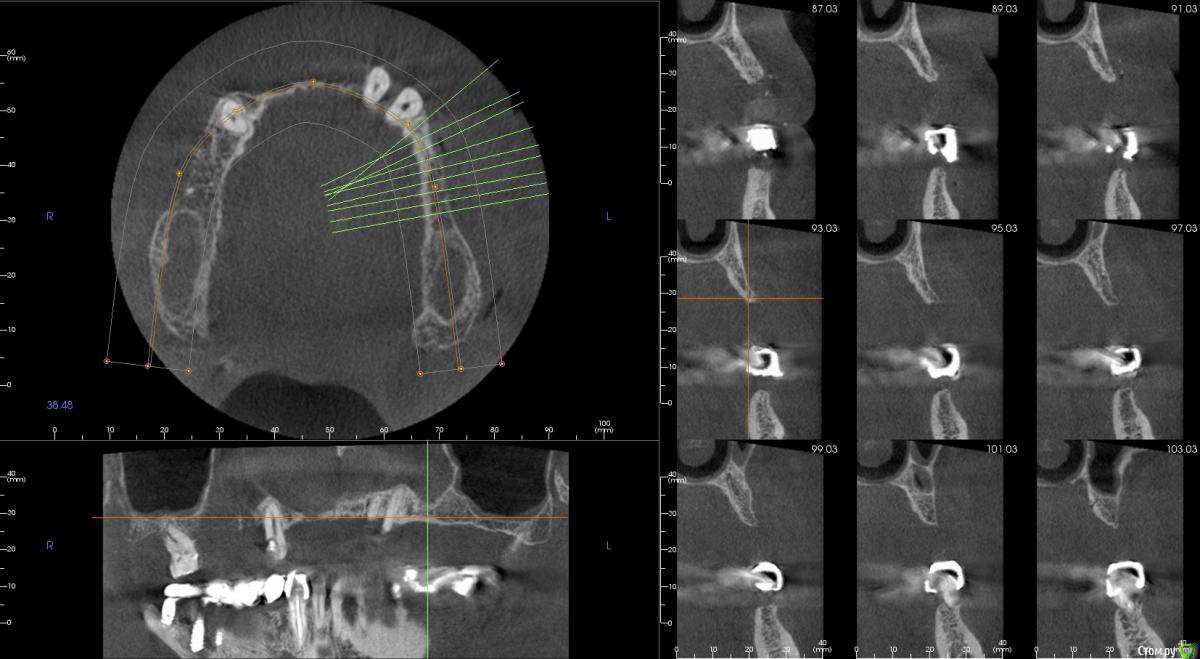

kamranchick Опубликовано 20 сентября, 2016 Поделиться Опубликовано 20 сентября, 2016 Интересует сторона 2. там хочу сделать соссидж, через несколько месяцев сделать закрытый синус и установить 2 винта в области 14 и 16, как вы думаете?и можно ли сделать конструкцию не брав во внимание фронтальный отдел? пациент финансово не тянет фронт Ссылка на комментарий

kamranchick Опубликовано 20 сентября, 2016 Автор Поделиться Опубликовано 20 сентября, 2016 Может убрать всё и на 4 ёх конструкцию предложить?думаю не получится, так как придется аугментировать и фронтальный отдел и боковой отдел чтобы по хорошему сделать все на 4, тем более я работаю на Осстем, а у нас мультиков в системе нет Ссылка на комментарий

колесников Опубликовано 20 сентября, 2016 Поделиться Опубликовано 20 сентября, 2016 думаю не получится, так как придется аугментировать и фронтальный отдел и боковой отдел чтобы по хорошему сделать все на 4, тем более я работаю на Осстем, а у нас мультиков в системе нетНе нужно там ничего аугментировать. Меняете корни на импланты. В обл премоляров так же есть объём по снимку. Иначе череда костных и мягкотканных пластик с неясным прогнозом. Пациент точно не потянет. У остема платформа 4.0 совместима с астровской 4.5-5.0. Можно у астры взять запчасти. Ссылка на комментарий